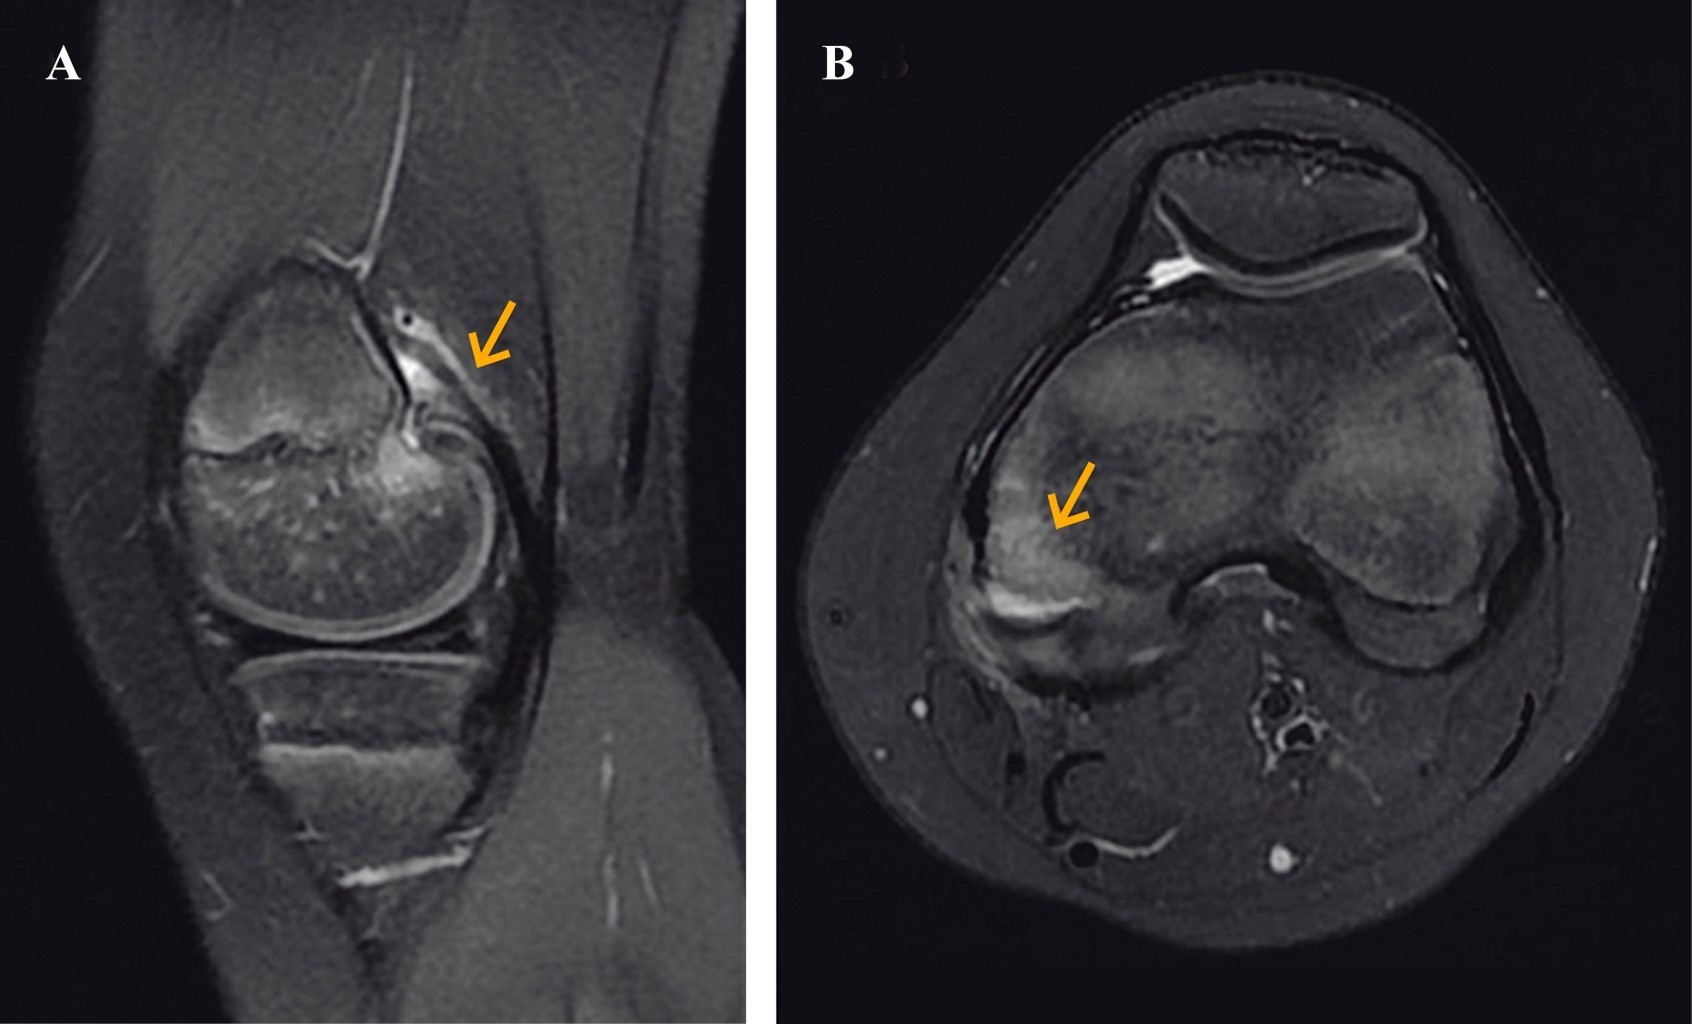

A 12-year-old female gymnast presented with acute pain on the back of her left knee sustained during training. Initial radiographs were unremarkable (Figure 1), prompting further imaging for a definitive diagnosis. A computed tomography (CT-scan) revealed the bone component of the lesion and the degree of displacement (Figure 2). Magnetic resonance imaging demonstrated an avulsion fracture at the posteromedial aspect of the femur arising from the origin of the tendon of the medial gastrocnemius muscle (Figure 3). There were no associated injuries or tears to the medial head of the gastrocnemius muscle.

Given the rarity of this condition, maintaining a high index of suspicion is paramount, particularly in patients presenting with pain localized to the popliteal fossa during hyperextension, difficulty with knee flexion, and minimal effusion. In high-energy trauma scenarios involving valgus and hyperextension forces, the possibility of posteromedial instability should prompt further investigation. X-rays alone may fail to detect this condition, necessitating the use of advanced imaging modalities. Magnetic resonance imaging, in particular, offers a comprehensive assessment by differentiating between potential diagnoses, identifying associated ligament or meniscal injuries, and detecting osteochondral fractures.15,16 Although CT lacks the sensitivity for soft tissue evaluation, it remains crucial for assessing the avulsion fragment's characteristics and planning surgical intervention, when necessary, especially through 3D reconstruction.17

Figure 3